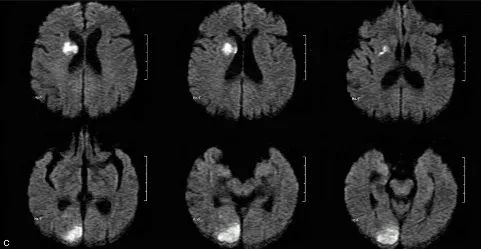

典型影像学表现:DWI 上病灶累及 3 个或 3 个以上血管分布区,常累及前后循环,双侧多见。排除其他明确的栓塞源或与这些病变相关的其他疾病。

↑ 多发梗死

1. 本病例影像学表现提示的诊断线索:青年女性,脑内新见散在多发病灶,散在分布于多个脑动脉供血区,包括幕上幕下,皮层及深部白质,无明显占位效应,病灶周围无水肿,弥散受限,增强扫描左枕叶较大病灶不均匀强化,余病灶无明显强化。